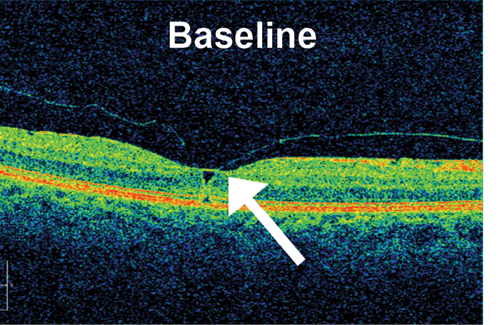

Results from this study suggest an alternative approach to pharmacologic vitreolysis (unpublished data). Although further data analysis is ongoing, roughly 65% of patients in the highest dose group in this dose-ranging study achieved the study’s primary endpoint of complete VMT release on OCT by day 90. Importantly, ALG-1001 was well tolerated, and no significant safety issues were seen. Injections of ALG-1001 can be repeated, and in this study up to three monthly injections were allowed. In patients in the 3.2-mg group (the highest dose tested), an average of 1.6 doses were required to achieve VMT release (Figure).

Figure. Example of VMT release in a patient at baseline (TOP) and after 90 days of follow-up after an injection of ALG-1001 3.2 mg (BOTTOM). Note the full separation of the posterior hyaloid membrane from the underlying retinal interface.